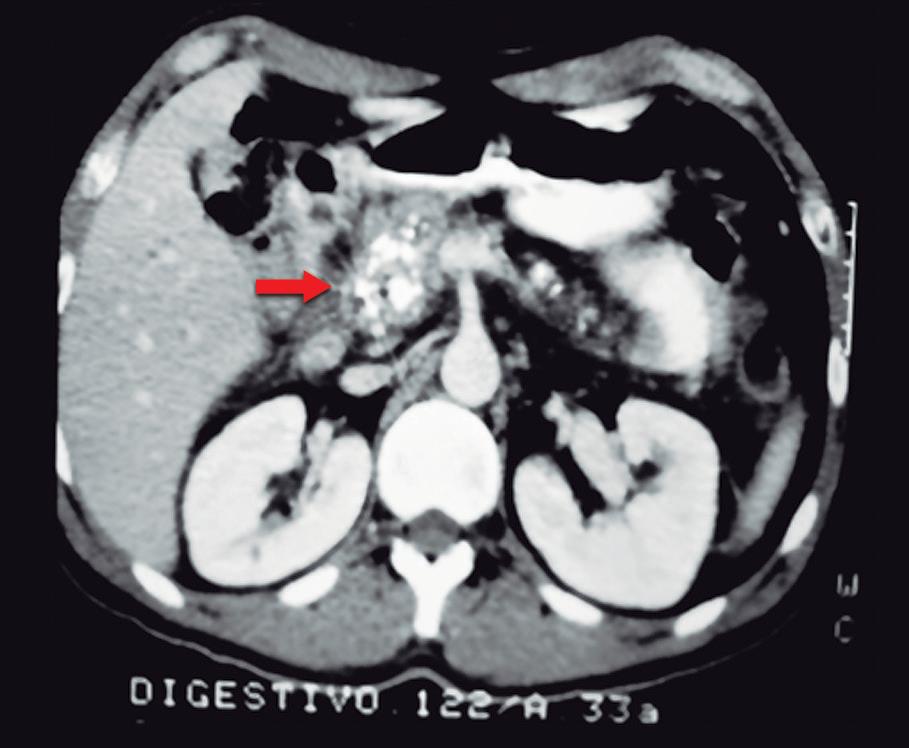

Paciente con vómitos en el periodo posoperatorio

Germán Francisco Rojas, Gabriel Adrián Mariño Camacho, Jesica Antonella Andruetto, Martín José Drago, Alejandro Moreira Grecco, Mariano Volpacchio, Esteban González Ballerga